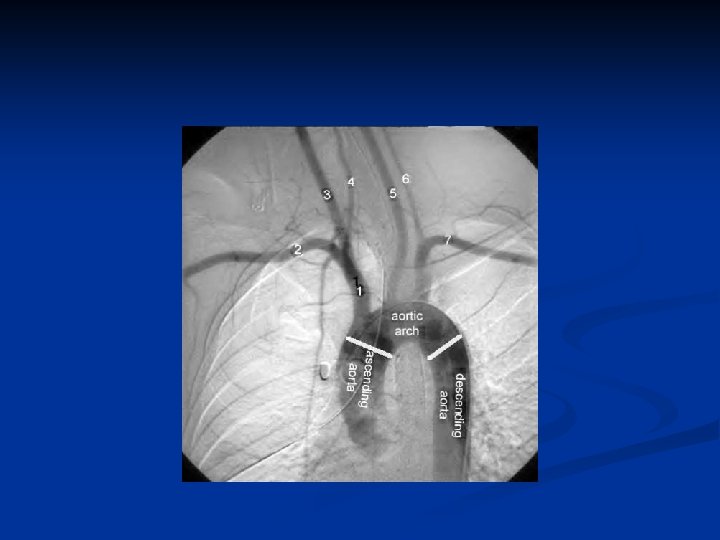

Anatomy n Aortic Arch n Innominate or Brachiocephalic artery n Right subclavian artery n Right common carotid Left common carotid artery n Left subclavian artery n n CCAs lie posterolateral to thyroid n Deep to sternocleidomastoid muscle n

Answers to previous slide Aortic arch angiogram n 1. Innominate art. n 2. Right subclavian art. n 3. Right common carotid art. n 4. Right vertebral art. n 5. Left common carotid art. n 6. Left vertebral art. n 7. Left subclavian art.